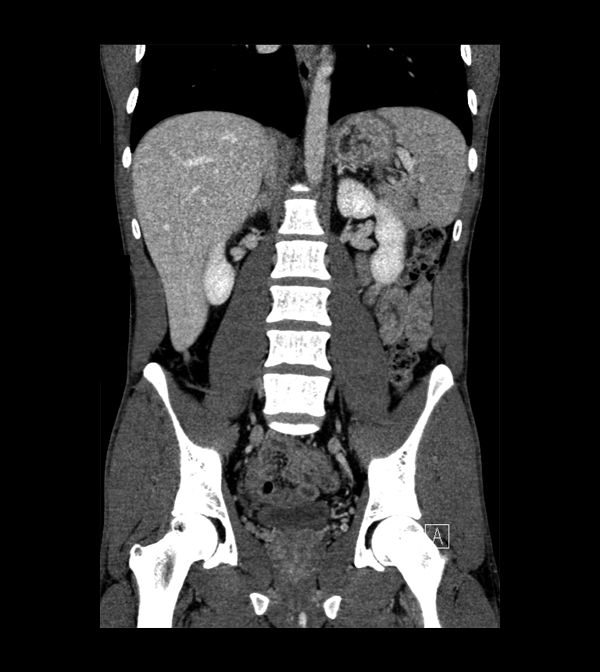

Body

Covers abdominal CT anatomy.